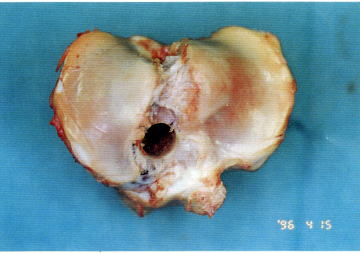

| 食肉用若豚の膝関節部にある中央部幅8mmの膝蓋腱である.膝蓋腱は、脛骨より直径13mm,長さ15mmの大きさの骨片(Bone

plug, BP)を残して切離した骨付き膝蓋腱(BTB)である |

| Fig.2 脛骨よりBone plugを切離 |

Fig.3 切離 した骨付き膝蓋腱 |